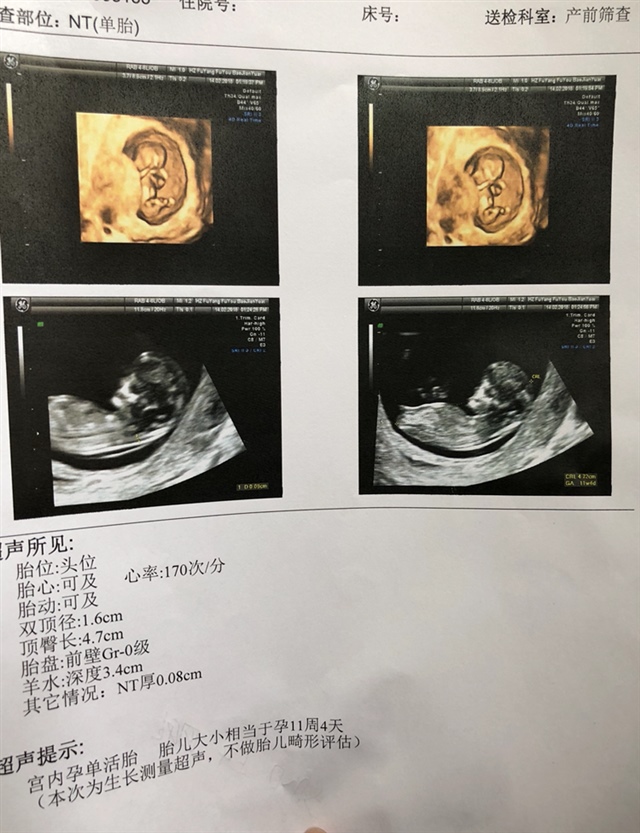

孕11周+2天

接nt顺利通过